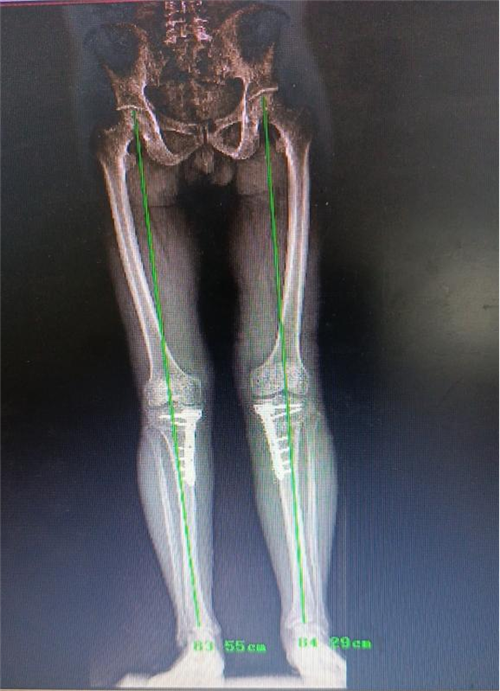

而近期患者感觉其左膝关节疼痛逐渐加重,伴随肿胀,甚至需要扶拐前行。因为患者对第一次手术效果非常满意,所以再次来到我院骨一科就诊。李强主任团队针对患者具体病情进行评估,发现患者负重位X线片显示左膝关节内侧间隙变窄,胫骨内翻,胫骨近端后倾角 76°,胫骨近端内侧角小于82°,左膝关节退行性改变。外侧间室及外侧关节间隙相对完好,测量后发现其畸形主要为关节内翻畸形。